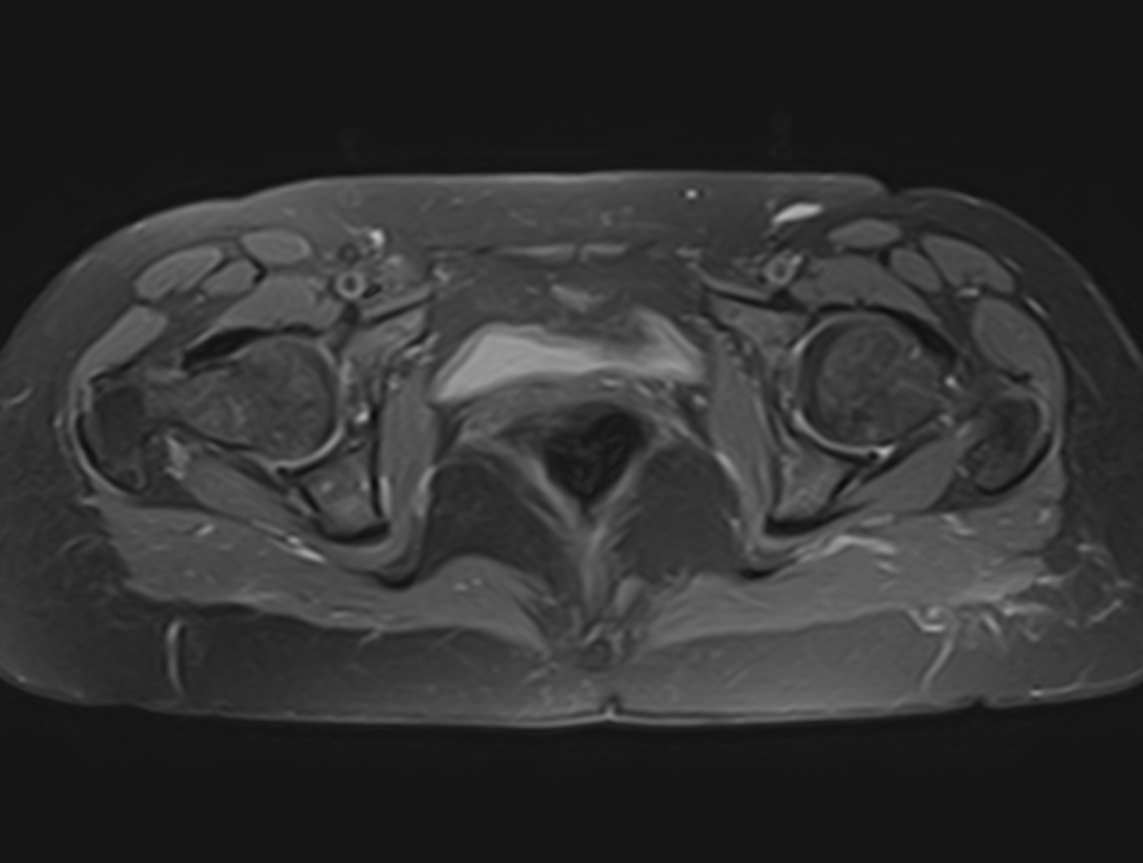

Максимально информативным способом диагностики заболеваний тазобедренных суставов является магнитно-резонансная томография. Кроме высокой информативности МРТ обладает такими преимуществами как достаточная быстрота, безболезненность, неинвазивность и безопасность. Метод основан на использовании действия на ткани внешнего магнитного поля, при этом не применяется вредное рентгеновское излучение. Поэтому МРТ можно проводить столько, сколько необходимо. Например, это бывает важно во время предоперационной подготовки и для динамического наблюдения в ходе лечения, в том числе, в послеоперационном периоде.

В клинике «Доступная медицина» МРТ тазобедренных суставов проводится на новейшем высокопольном томографе экспертного класса TOSHIBA VANTAGE TITAN 1,5 Тесла. Томограф производит сканирование зоны исследования, делая послойные срезы в разных плоскостях с шагом от 1 мм, затем с помощью цифровых приложений преобразует полученные данные в трехмерные изображения превосходного качества. МР томография дает детальную информацию о состоянии костных структур сустава, сухожилий, связочного аппарата, синовиальной оболочки, суставной полости, нервов, сосудов и прилегающих мягких тканей. Это позволяет поставить точный и достоверный диагноз и назначить вовремя лечение.